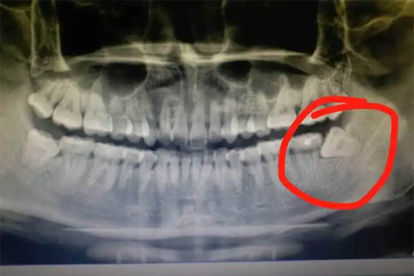

智齿横长通常建议拔除。智齿横长在医学上称为水平阻生智齿,是指智齿的生长方向与邻牙呈水平角度,完全埋伏或部分埋伏在牙槽骨内。

智齿横长容易导致邻牙龋坏,智齿与邻牙之间形成难以清洁的间隙,食物残渣滞留引发细菌滋生,逐渐腐蚀邻牙牙体组织形成龋洞。可能引起邻牙牙根吸收,横长智齿持续压迫邻牙牙根,导致牙根表面骨质被破坏,严重时造成邻牙松动。可能诱发智齿冠周炎,部分萌出的智齿与牙龈形成盲袋,细菌在此繁殖引发急性炎症,表现为牙龈红肿疼痛、张口受限等症状。可能造成牙列拥挤,横长智齿在萌出过程中产生向前推力,逐渐导致前牙排列不齐。可能形成含牙囊肿,长期埋伏的智齿周围组织发生病变,发展为颌骨囊肿破坏骨质结构。